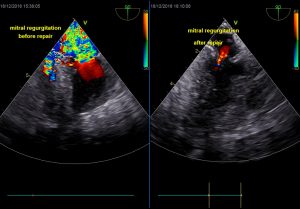

La plupart des chiens ne prendront plus de traitement trois mois après l’intervention. On observe au niveau du cœur une réduction de la taille des cavités (sauf en général stade D), une diminution significative de la régurgitation mitrale qui devient beaucoup plus faible, permettant à votre chien de vivre correctement sans difficulté respiratoire ni fatigabilité impactant sa qualité de vie. Certains chiens opérés trop tardivement garderont du pimobendane +/- du sildénafil à vie.

Photos sur la droite : réparations mitrales effectuées par Dr JH Bozon. En haut : Echographie Transoesophagienne per-opératoire (Dr Sabine Bozon). En bas : Echographie trans-thoracique post-opératoire (Dr Sabine Bozon)